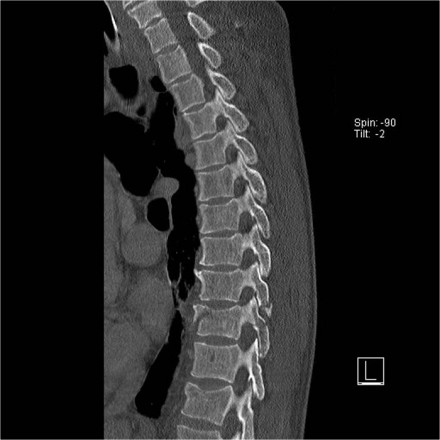

The images are of a patient with a typical bamboo spine as a result of ankylosing spondylitis.

After a fall on his back no fracture was seen on the x-rays.

However the CT shows a thin fracture line through the anterior side of the vertebral body and also through the spinous process.

Continue with the MR-images.